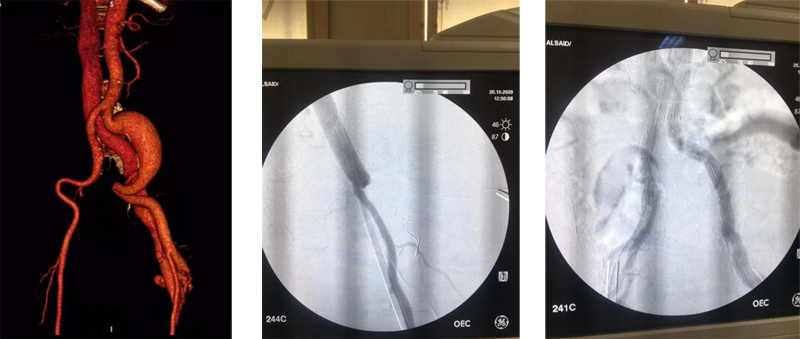

أعلن الأستاذ الدكتور/ علاء عطية - عميد الكلية عن نجاح فريق طبى بقسم جراحة الأوعية الدموية بكلية الطب جامعة اسيوط مكون من الأستاذ الدكتور/ أيمن حسب الله والأستاذ الدكتور/ أحمد حسن بكر والأستاذ الدكتور/ هيثم على حسن والأستاذ الدكتور/ محمود اسماعيل فى علاج أحد الحالات المعقدة والنادرة على مستوى العالم وهو مريض يعانى من ناسور شرياني وريدى فى الساق نتيجة طلق ناري منذ ١٥ عام وفى نفس الوقت يعانى من وجود تمدد ضخم بالشريان الحرقفى الأيسر. وتم علاج المريض بتقنية مشتركة مابين التدخل الجراحى والقسطرة التداخلية حيث تم غلق الناسور بواسطة الربط الجراحي وإستخدام ملفات حلزونية وتم التعامل مع التمدد الشريانى بواسطة القسطرة التداخلية وتركيب الدعامات المغطاة. وأوضح الأستاذ الدكتور/ مصطفى سعد - رئيس قسم جراحة الأوعية الدموية أن صعوبة الحالة فى تزامن وجود الناسور الشريانى مع التمدد الانيورزمى فى نفس الوقت وفى نفس الطرف مما يعرض حياة المريض للخطر. وتعتبر إستخدام التدخل الجراحى مع القسطرة التداخلية هى الحل الأمثل فى مثل هذه الحالات. |